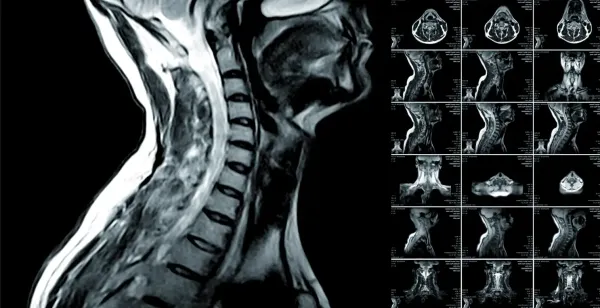

Магнитно-резонансная томография назначается врачами для постановки точного диагноза при различных патологических процессах в организме. Это один из самых эффективных диагностических методов, который позволяет выявить наличие заболеваний. При прохождении МРТ человек не получает волновую нагрузку, как при КТ, а визуализация изображения происходит за счет действия магнитного поля и радиоволн. Благодаря этому, специалист получает полную картину патологии внутренних органов, описывает ее и назначает лечение.

МРТ проводится с помощью новейших аппаратов, как правило, томографами немецкого производства Siemens Symphony 1.5T. Удобство их применения заключается в хорошем освещении и возможности проветривания. Метод МРТ отличается высокой сложностью, но его доказанная безопасность в некоторых случаях является единственным информативным методом диагностики.

Процедура выполняется следующим образом: пациент ложится на подвижный стол, который затем помещается в туннель, где создается магнитное поле высокой мощности. Радиочастотные импульсы направляются на конкретную область тела, которую необходимо визуализировать. На такое воздействие реагируют атомы водорода, содержащиеся в молекулах воды в каждой клеточке человеческого организма.

Существуют нормальные показатели содержания атомов водорода в здоровых тканях и их отклонения. О формировании патологического процесса свидетельствует большее количество атомов, нехарактерное для данного органа. Данные об атомном резонансе считываются катушками, обрабатываются компьютерной программой, которая создает визуальное изображение органа на срезе и в деталях.